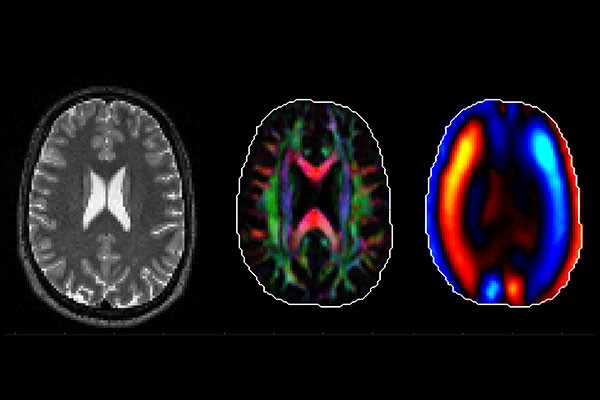

Bayly and his team will use several forms of imaging at the Neuroimaging Lab Research Center and the Small Animal Magnetic Resonance Facility in the Mallinckrodt Institute of Radiology at Washington University School of Medicine to study the behavior of the brain and skull in a preclinical model and to take measurements of the interactions between a helmet, the skull and the brain in healthy volunteers. Results of the imaging also will allow them to study the direction-dependent mechanical properties of brain tissue.

“We are looking at how shear waves move in the brain,” Bayly said. “A blast from an explosion creates a big pressure wave in air, which is transmitted into the skull potentially creating large, damaging, shear waves in the brain. In our experiments, we will generate small, non-injurious shear waves to probe how the brain might respond to blasts and other sources of skull motion.”